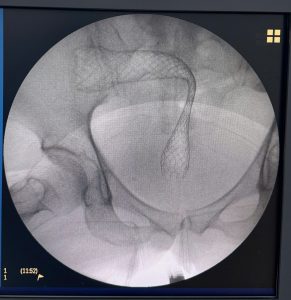

ThS. BS. Nguyễn Văn Khoa đã tư vấn lợi điểm cũng như tai biến, biến chứng và nhận được sự nhất trí cao từ bệnh nhân để tiến hành đặt stent kim loại tự bung qua vị trí khối u, giúp giải áp và khơi thông đường tiêu hóa. Ca can thiệp được thực hiện bởi BS.CKII. Đinh Đức Minh trong khoảng 60 phút. Sau hai tuần điều trị, bệnh nhân xuất viện trong tình trạng ổn định, có thể tự đi lại được và tinh thần khá lên để tiếp tục phác đồ điều trị ung thư trực tràng.

Hình ảnh trực tràng đã được đặt stent thành công